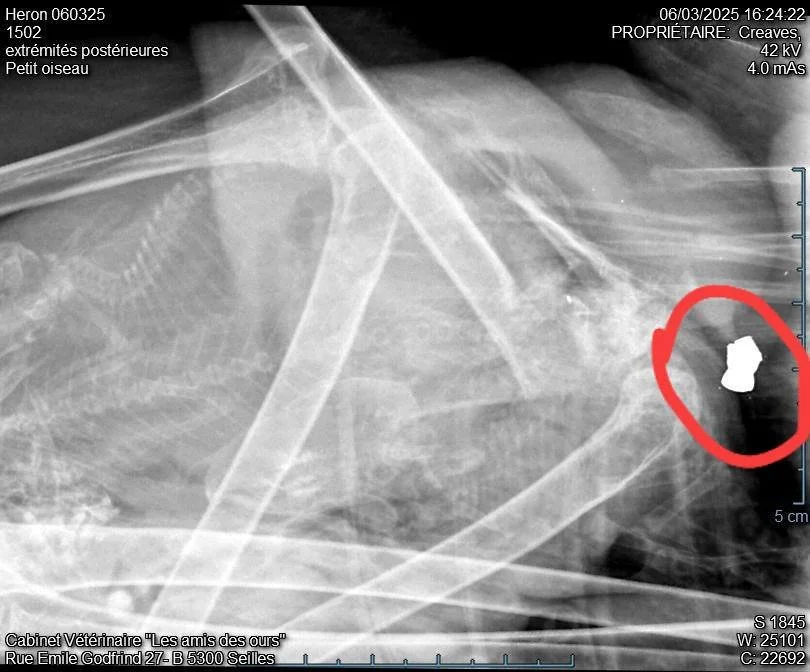

Ce héron, trouvé en zone péri-urbaine andennaise, souffre d'une fracture du tibio-tarse dûe à un tir illégal.

La radiographie effectuée par notre vétérinaire est sans équivoque...il est victime d'un tir.